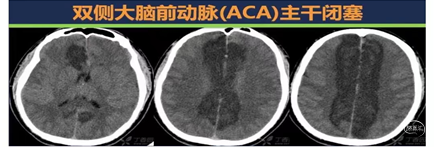

二、大脑前动脉血栓取栓

先复习一下大脑前动脉解剖知识:

大脑前动脉主要分支为:眶动脉、额极动脉、额叶内动脉、拼周动脉、胖缘动脉主要供应大脑半球内侧面的3/4和额顶叶背侧面上1/4皮质和皮质下白质,深穿支的主要供血区域为内囊膝部和内囊后肢前2/3、壳核、苍白球和尾状核。

大脑前动脉是重要功能区域,血管闭塞常见表现:

1、运动障碍(90%,和旁中央小叶辅助运动区受累有关)。

2、情感淡漠(和额极、直回、胖抵体、扣带回受累有关)。

3、尿失禁(旁中央小叶)。

4、失语。

5、感觉障碍(拼周和胖缘动脉)。

典型病例1 3*20小支架联合5F中间导管用于A2段SWIM取栓

------资料来源 姚力

病例简介

患者男,59岁,右侧肢体活动不灵1小时25分钟。神经系统:神志清楚,反应迟钝,言语基本流利,双侧额纹、鼻唇沟对称,伸舌左偏,四肢肌张力正常,右上肢肌力3级,右下肢肌力2级,右侧巴氏征(+)。NIHSS评分9分。 ASPECTS-CT评分:前循环9分。MRI显示左侧大脑前动脉区域埂塞可能,MRA大脑前动脉A2以远未显影。

初步诊断:1.急性脑梗死(左侧大脑前动脉);TOAST分型:大动脉粥样硬化型);2.高血压病3级,很高危;3. 2型糖尿病。

造影右侧大脑前动脉缺如(未发育),左侧大脑前A2段闭塞。